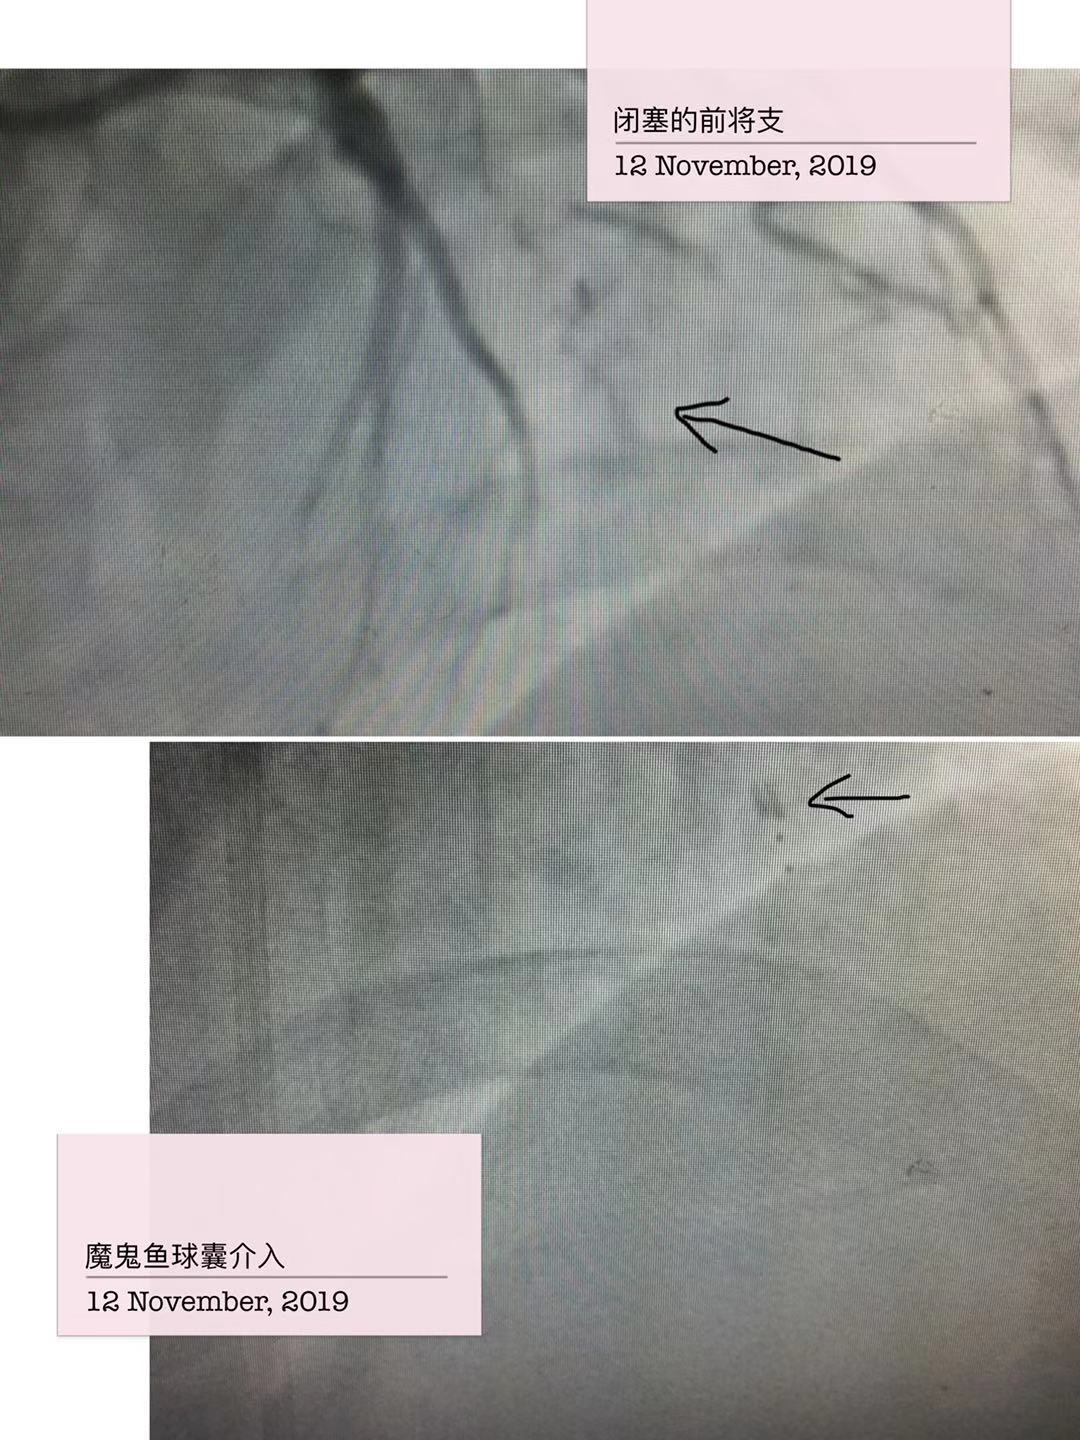

经过充分的术前准备,2019年10月23日由赵朝主任、陆艳副主任进行冠状动脉造影检查,结果显示冠状动脉严重三支病变,左前降支近段100%闭塞,间隔支向左前降支远段形成侧支循环;回旋支中段100%闭塞,右冠状动脉全程瘤样扩张,远端95%以上狭窄,右向左侧支循环很差(逆向技术使用概率很小)。决定先处理最重要的左前降支。正向技术尝试半小时左右失败,由于CTO闭塞残端开口不清、且自认为有较好的同侧间隔支逆向,转换为同侧逆向技术,由于近远端交通的间隔支血管过度迂曲,导丝尝试3个小时左右均不能到达前降支远段。不认输的我们再次转变术式,在血管内超声的指导下,超滑加硬导丝正向刺破闭塞处纤维帽,及时导丝降级,然而导丝不幸进入血管夹层,双腔微导管、手工ADR反复尝试不能回到远段血管真腔,造影剂已经接近300mL,看来只剩下ADR技术。ADR技术是通过输送stingray球囊到良好着陆区的血管夹层内,通过两个相反方向的标识,使硬导丝重回血管真腔的操作。严格按照流程,多次不懈的尝试,功夫不负有心人,导丝回到了前降支远段血管真腔,接下来就是常规操作,手术圆满成功,整个手术历时超过6小时。